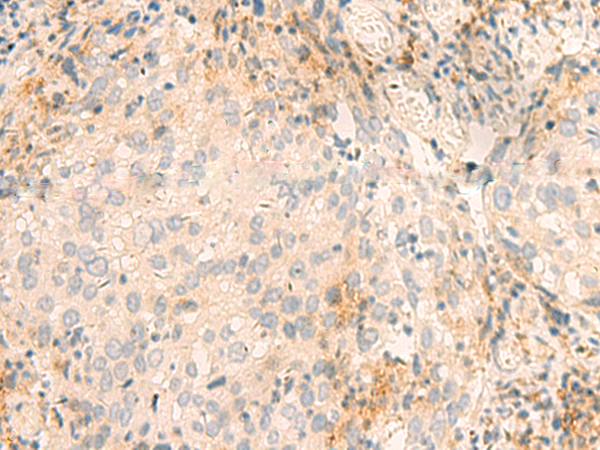

分类: 科研抗体货号: P03026别名: PSF2; Pfs2; HSPC037应用: IHC反应种属: Human, Mouse